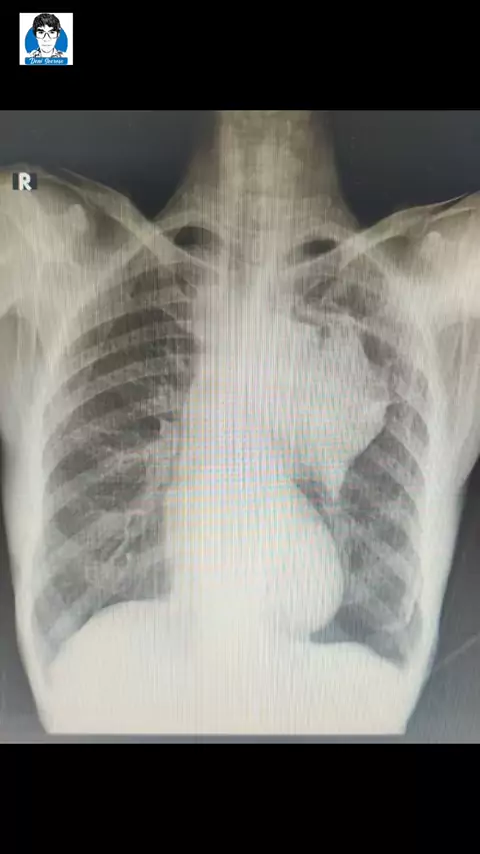

Pasien Kanker Paru dikemoterapi dengan obat Karboplatin+Premetexed 6 siklus#kankerparu#lungcancer#onkologiparumedan#onkologiparumedan#denisoeroso#dokterparu#viral#edukasi#゚#